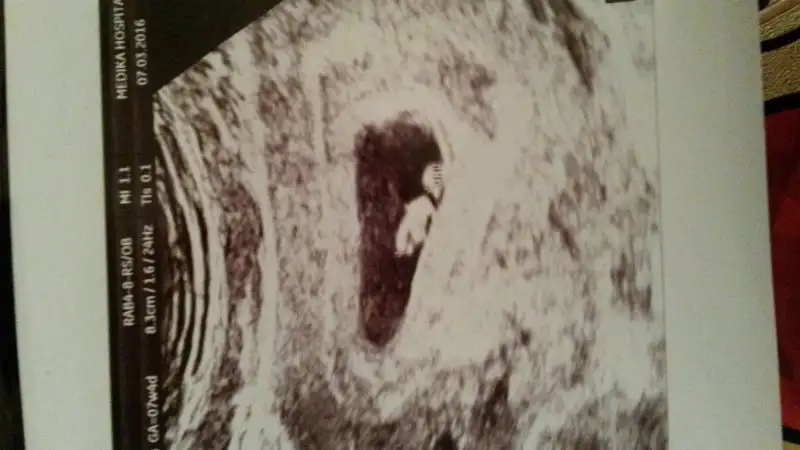

Erkek sankiEki Görüntüle 1790261 buda benim meleyim kizlar cinsiyet tahmini yaparmisiniz

Ayyy evet baska bir forumdada gosterdim ordaki bayanda erkek soyledi hadi hayirlisi bir oğlum var galiba ikincide yoldaErkek sanki![]()

Banada kiz gibi geldi cnm hayirli saglikli olsun bebeğin.Ayyy evet baska bir forumdada gosterdim ordaki bayanda erkek soyledi hadi hayirlisi bir oğlum var galiba ikincide yolda

Merhaba canımSanırım cinsiyet tahmini yapıyorsunuz benim 3. Miniğim 2 kuzım var rica etsem benim bebişime de bakarmısınızErkek sanki![]()